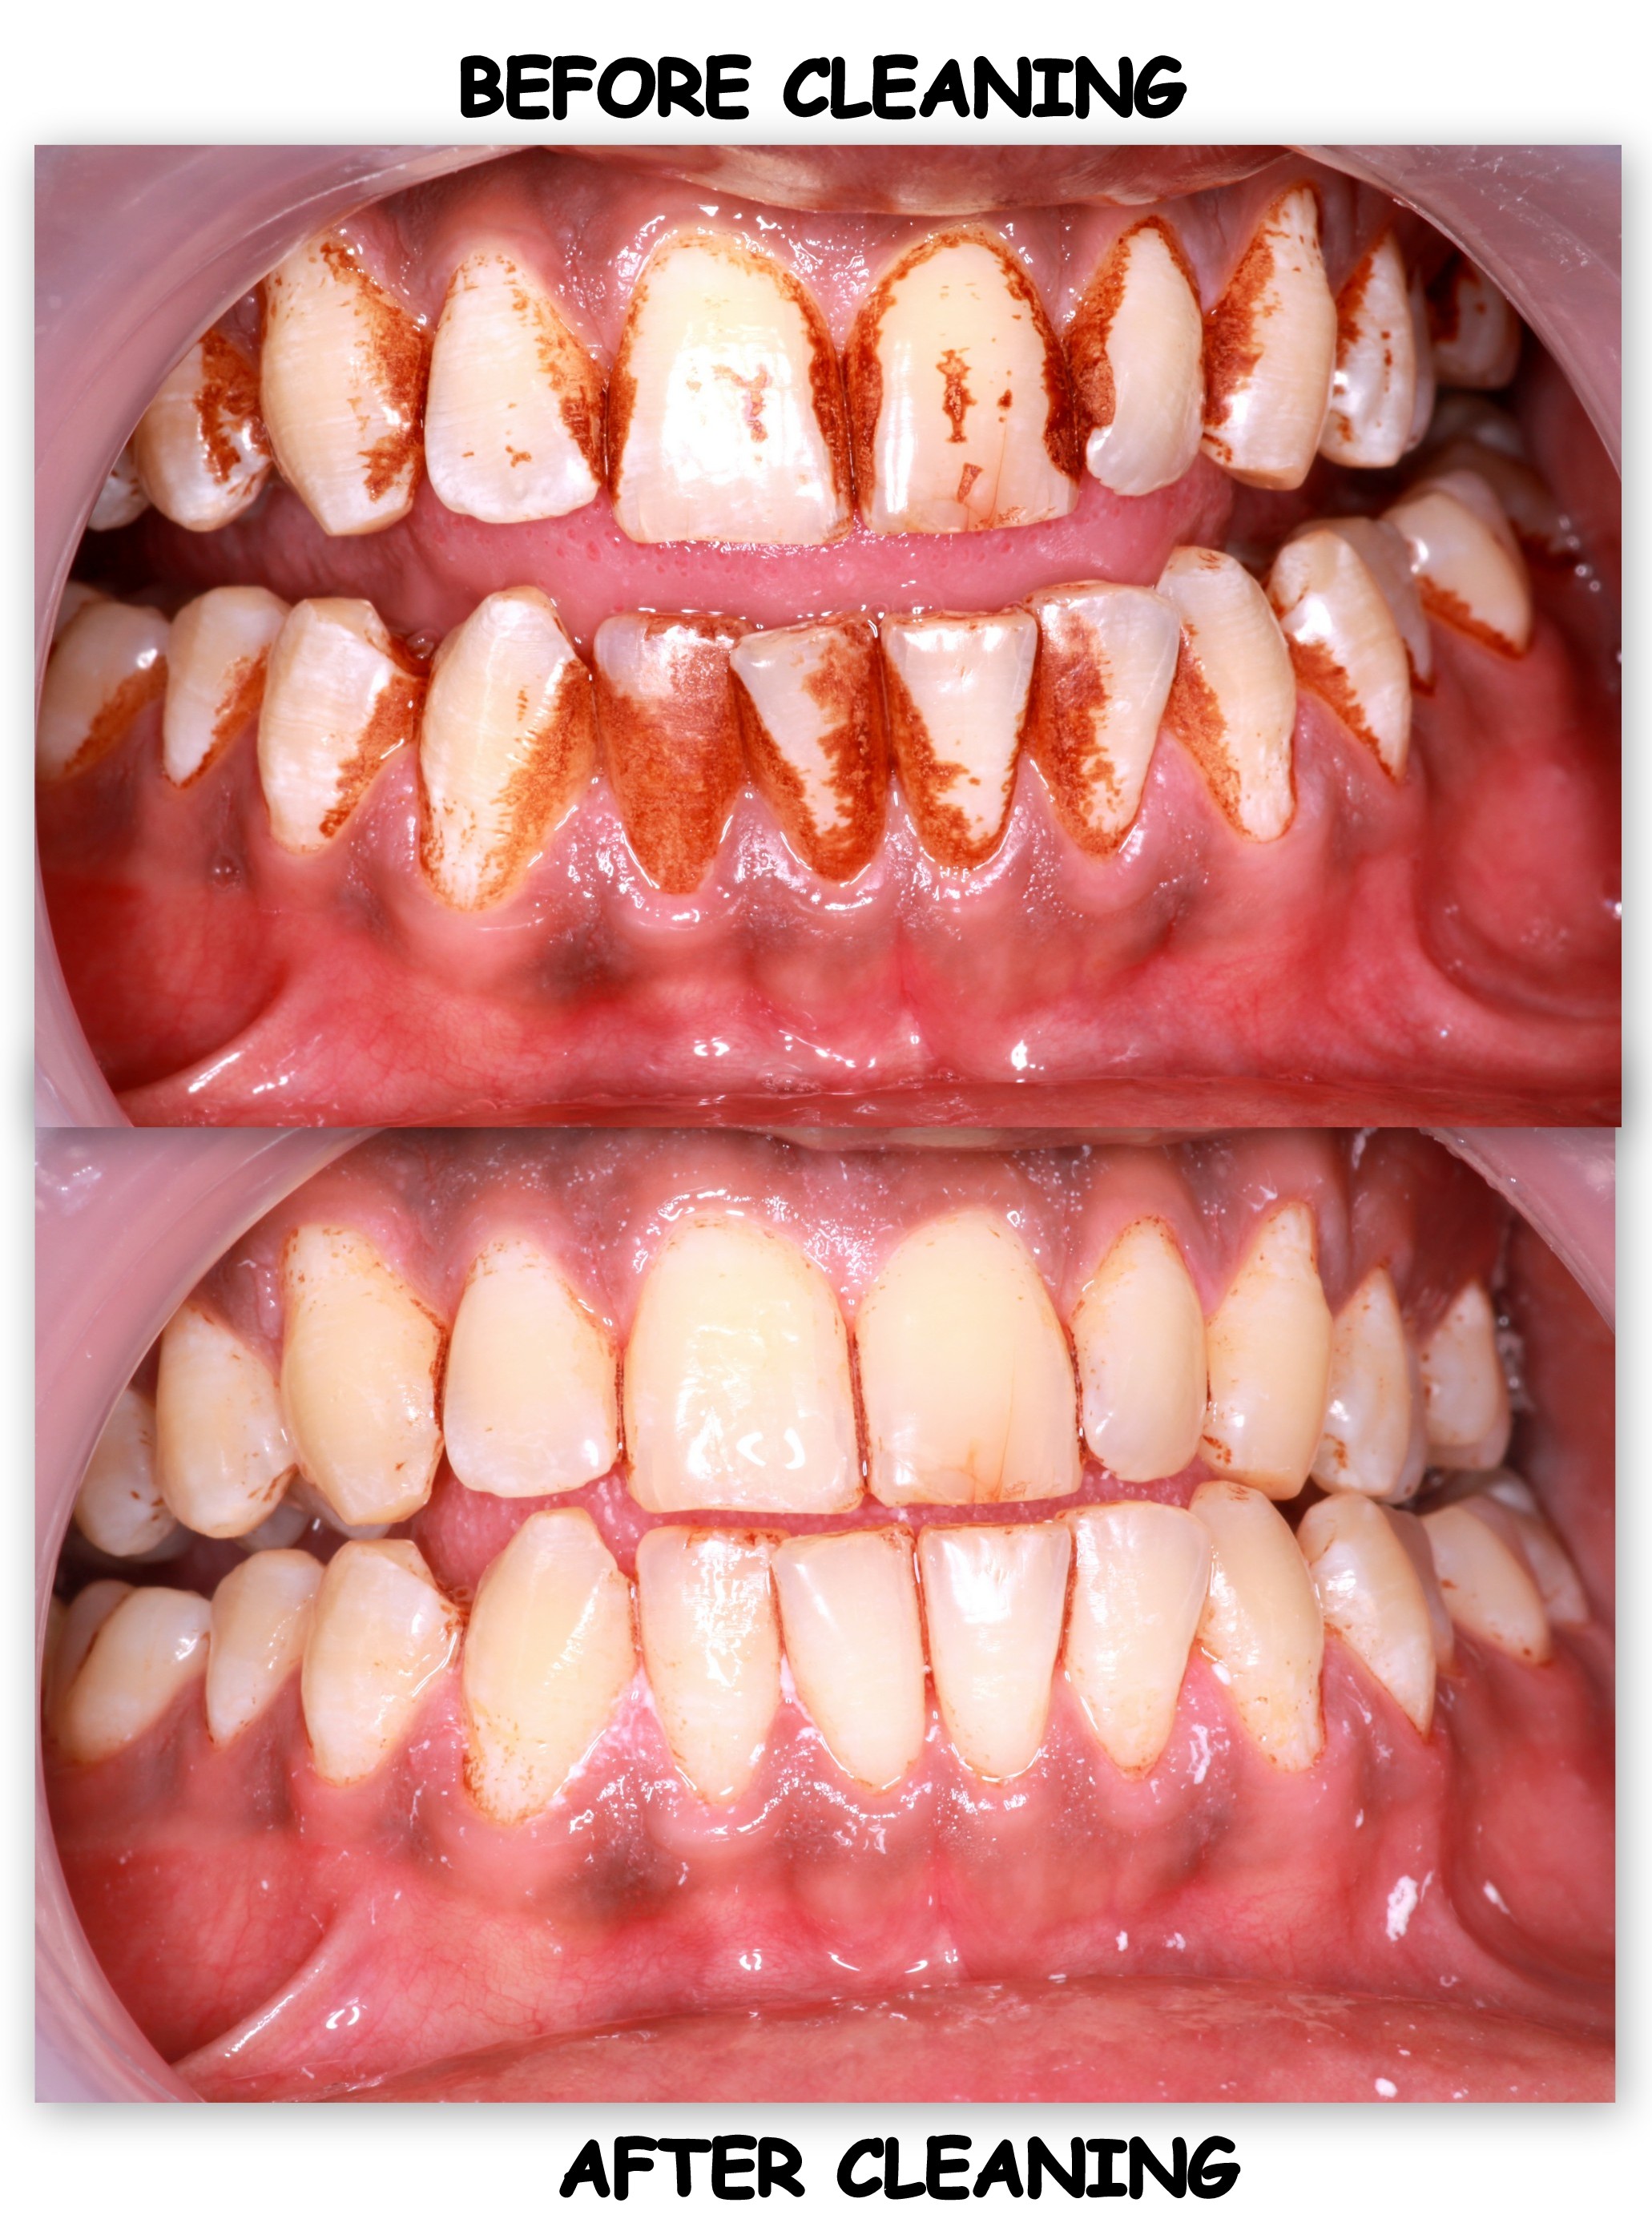

ORAL PROPHYLAXIS(Professional cleaning)

Regular 6 monthly check-up and cleaning is a must for healthy gums and a well integrated oral cavity. The procedure is non abrasive without any harm to the enamel as removal of plaque, stains, and tartar is done superficially with ultrasonic instruments.

Oral prophylaxis means tooth cleaning by your dentist and is a mandatory dental procedure to be done every 6 months. It is highly recommended for those patients who have extrinsic stains due to smoking tobacco, betel nut chewing etc, who have tartar accumulation due to unwanted food particles which leads to bad breath - a common complain of a patient and in cases of bleeding gums and infections.

The procedure usually requires only one office visit. But two or three sessions can be required varying from case to case. The dentist will use an ultrasonic cleaning tip in all the areas where the tooth brush can't reach. The vibration makes the tartar and stains loosen off from the teeth and gums. Polishing is done to get a sparkle in your teeth after cleaning is done.